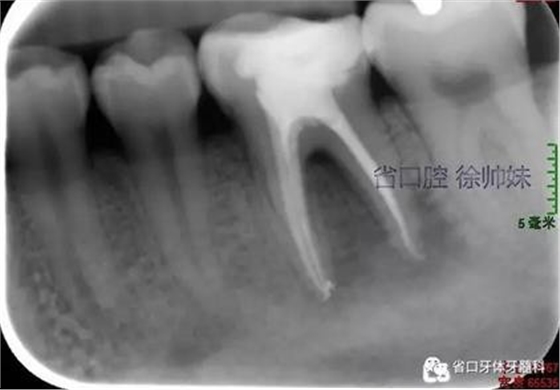

處理:36橡皮障隔濕,顯微鏡下去除封藥,沖洗根管,超聲蕩洗,熱牙膠連續(xù)波加壓充填根管(AH-PLUS),玻璃離子墊底,自酸蝕粘接,納米樹脂充填,調(diào)合,拋光。頰側牙周袋內(nèi)沖洗,置牙康。根尖片(圖3)顯示恰填,囑勿用患牙咬硬物,定期復查。

圖3 根充片